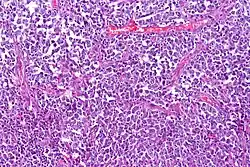

Lymphoma cancer types have varying probabilities of metastasizing to the CNS, resulting in secondary CNS lymphoma (SCNSL), which may appear simultaneously as systemic lymphoma, or as remission after systemic lymphoma is treated. Synchronous, or de novo disease is diagnosed in approximately 40% of patients and relapse in 60%.[8] Overall, CNS involvement is observed in 2 to 27% of patients with aggressive systemic non-Hodgkin's lymphoma.[5] 5% of patients with diffuse large B cell lymphoma, the most common type of non-Hodgkin lymphoma, result in SCNSL but account for most SCNSL cases.[3]